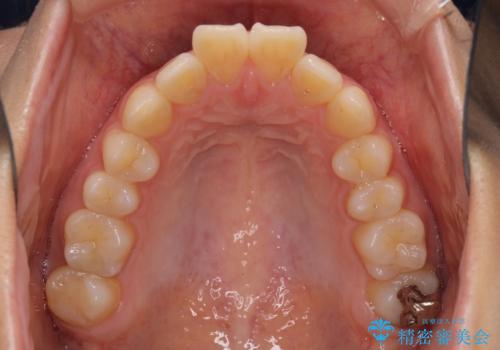

- 前方に傾斜した上下の前歯を気にして来院された患者様です。

唇の閉じにくさや横顔のシルエットが気になるような突出感ではなかったため、インビザラインを用いて、歯列の遠心移動とIPR(歯と歯の間を削る)により前歯の傾斜を改善していくこととしました。

スムーズに終了すると思われましたが、インビザライン矯正独特の奥歯が咬み合わない状態が続き、更には遠方へ転居されたこともあり、治療期間は長引いてしまいました。